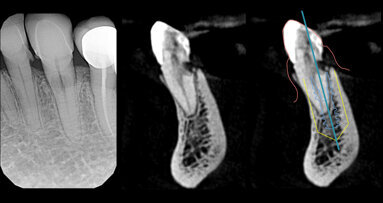

La Socket-Shield Technique (SST) è una procedura ormai consolidata, che ha già 13 anni di letteratura ed è sostenuta in Italia da una ...